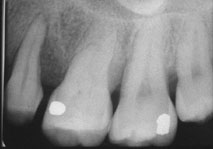

治療前牙周有環狀骨缺損,牙齒動搖。

治療後12個月牙周骨再生,牙齒穩固。